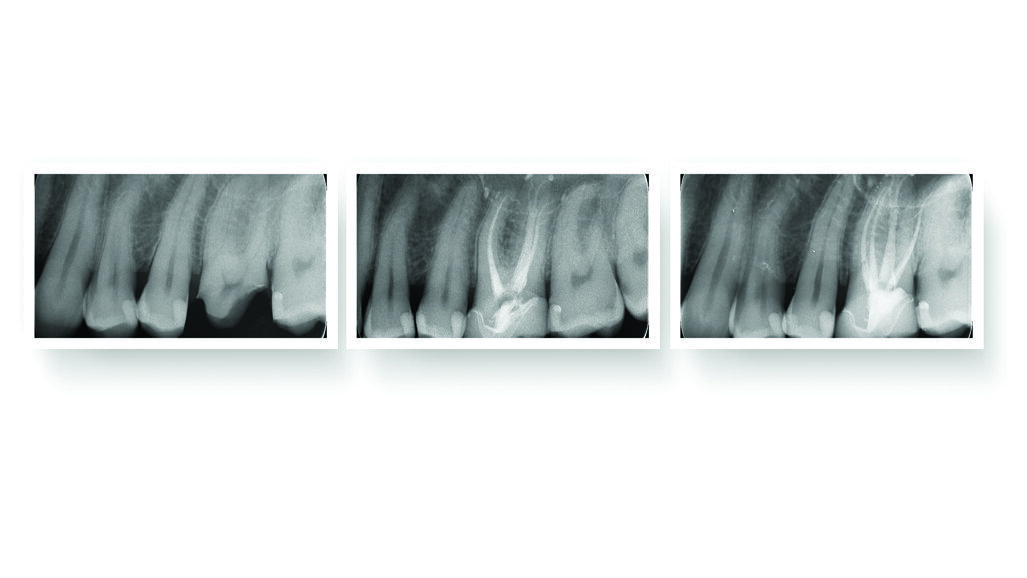

One of Fotona’s most groundbreaking advancements is SWEEPS (Shock Wave Enhanced Emission Photoacoustic Streaming) — an advanced endodontic solution designed to thoroughly clean, debride and decontaminate complex root canal systems, including lateral canals and dentinal tubules.

Fotona advanced laser technologies, SSP and Fotona SWEEPS, utilize the Er:YAG wavelength to deliver superior root canal cleaning and irrigation. SSP creates non-thermal, photoacoustic waves for effective smear layer removal, while Fotona SWEEPS enhances irrigation and decontamination using synchronized ultra-short pulses to generate powerful shockwaves even in the narrowest of canals.

The patented R-SWEEPS mode allows customizable settings, optimizing laser-activated irrigation for maximum efficacy and pressure generation without risking apical extrusion. Together, these innovative technologies set a new standard for laser-assisted endodontic treatments.

Fotona’s third-generation Adaptive Structured Pulse (ASP) technology is the only laser platform capable of generating the Fotona SWEEPS process. This innovative method precisely times a secondary laser pulse to accelerate bubble collapse, producing primary and secondary shockwaves that enhance cleaning efficiency.

“The Fotona LightWalker has provided cutting edge technology to enhance treatments that I perform daily,” said Dr. Mark O’Banion, DMD. “Fotona’s SWEEPS technology macroscopically and microscopically cleans the root canal system including isthmus, fins and dental tubules and addresses areas that standard irrigation cannot reach. I feel confident that I have performed the best endodontic care possible, both surgically and non-surgically, when utilizing this laser’s acoustic streaming technique.”